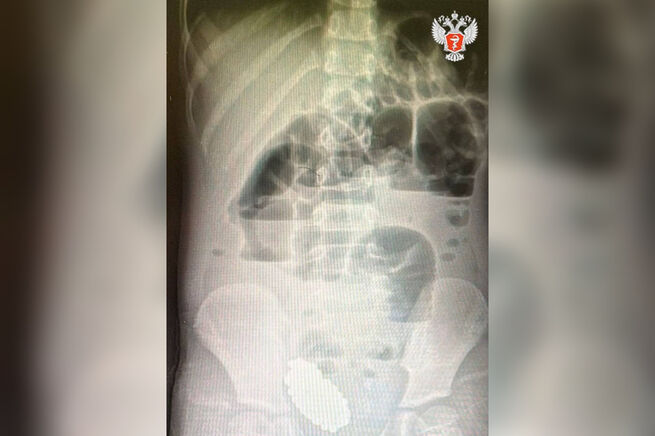

В Волгограде медики провели операцию на маленькой пациентке, которая съела 134 магнитных шарика. Сначала у нее проявились симптомы ОРВИ и боли в животе, и родители решили лечить ее самостоятельно. Однако через шесть дней самочувствие девочки ухудшилось и ей потребовалась госпитализация.

Как сообщает пресс-служба Минздрава России, при обследовании была выявлена кишечная непроходимость из-за инородного тела, которое сжимало стенки кишечника.